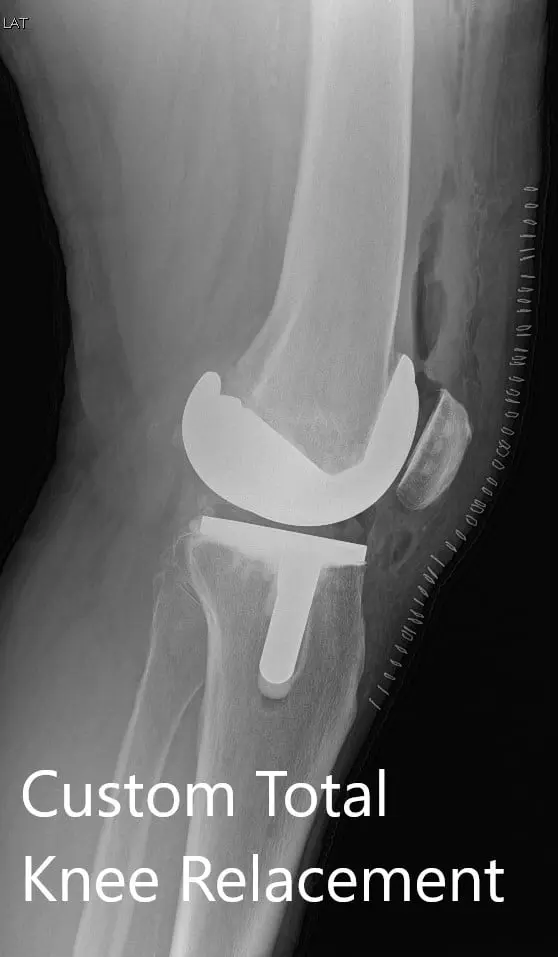

Postoperative X-ray showing AP and lateral views of the right knee

Postoperative X-ray showing AP and lateral views of the right knee - img 2